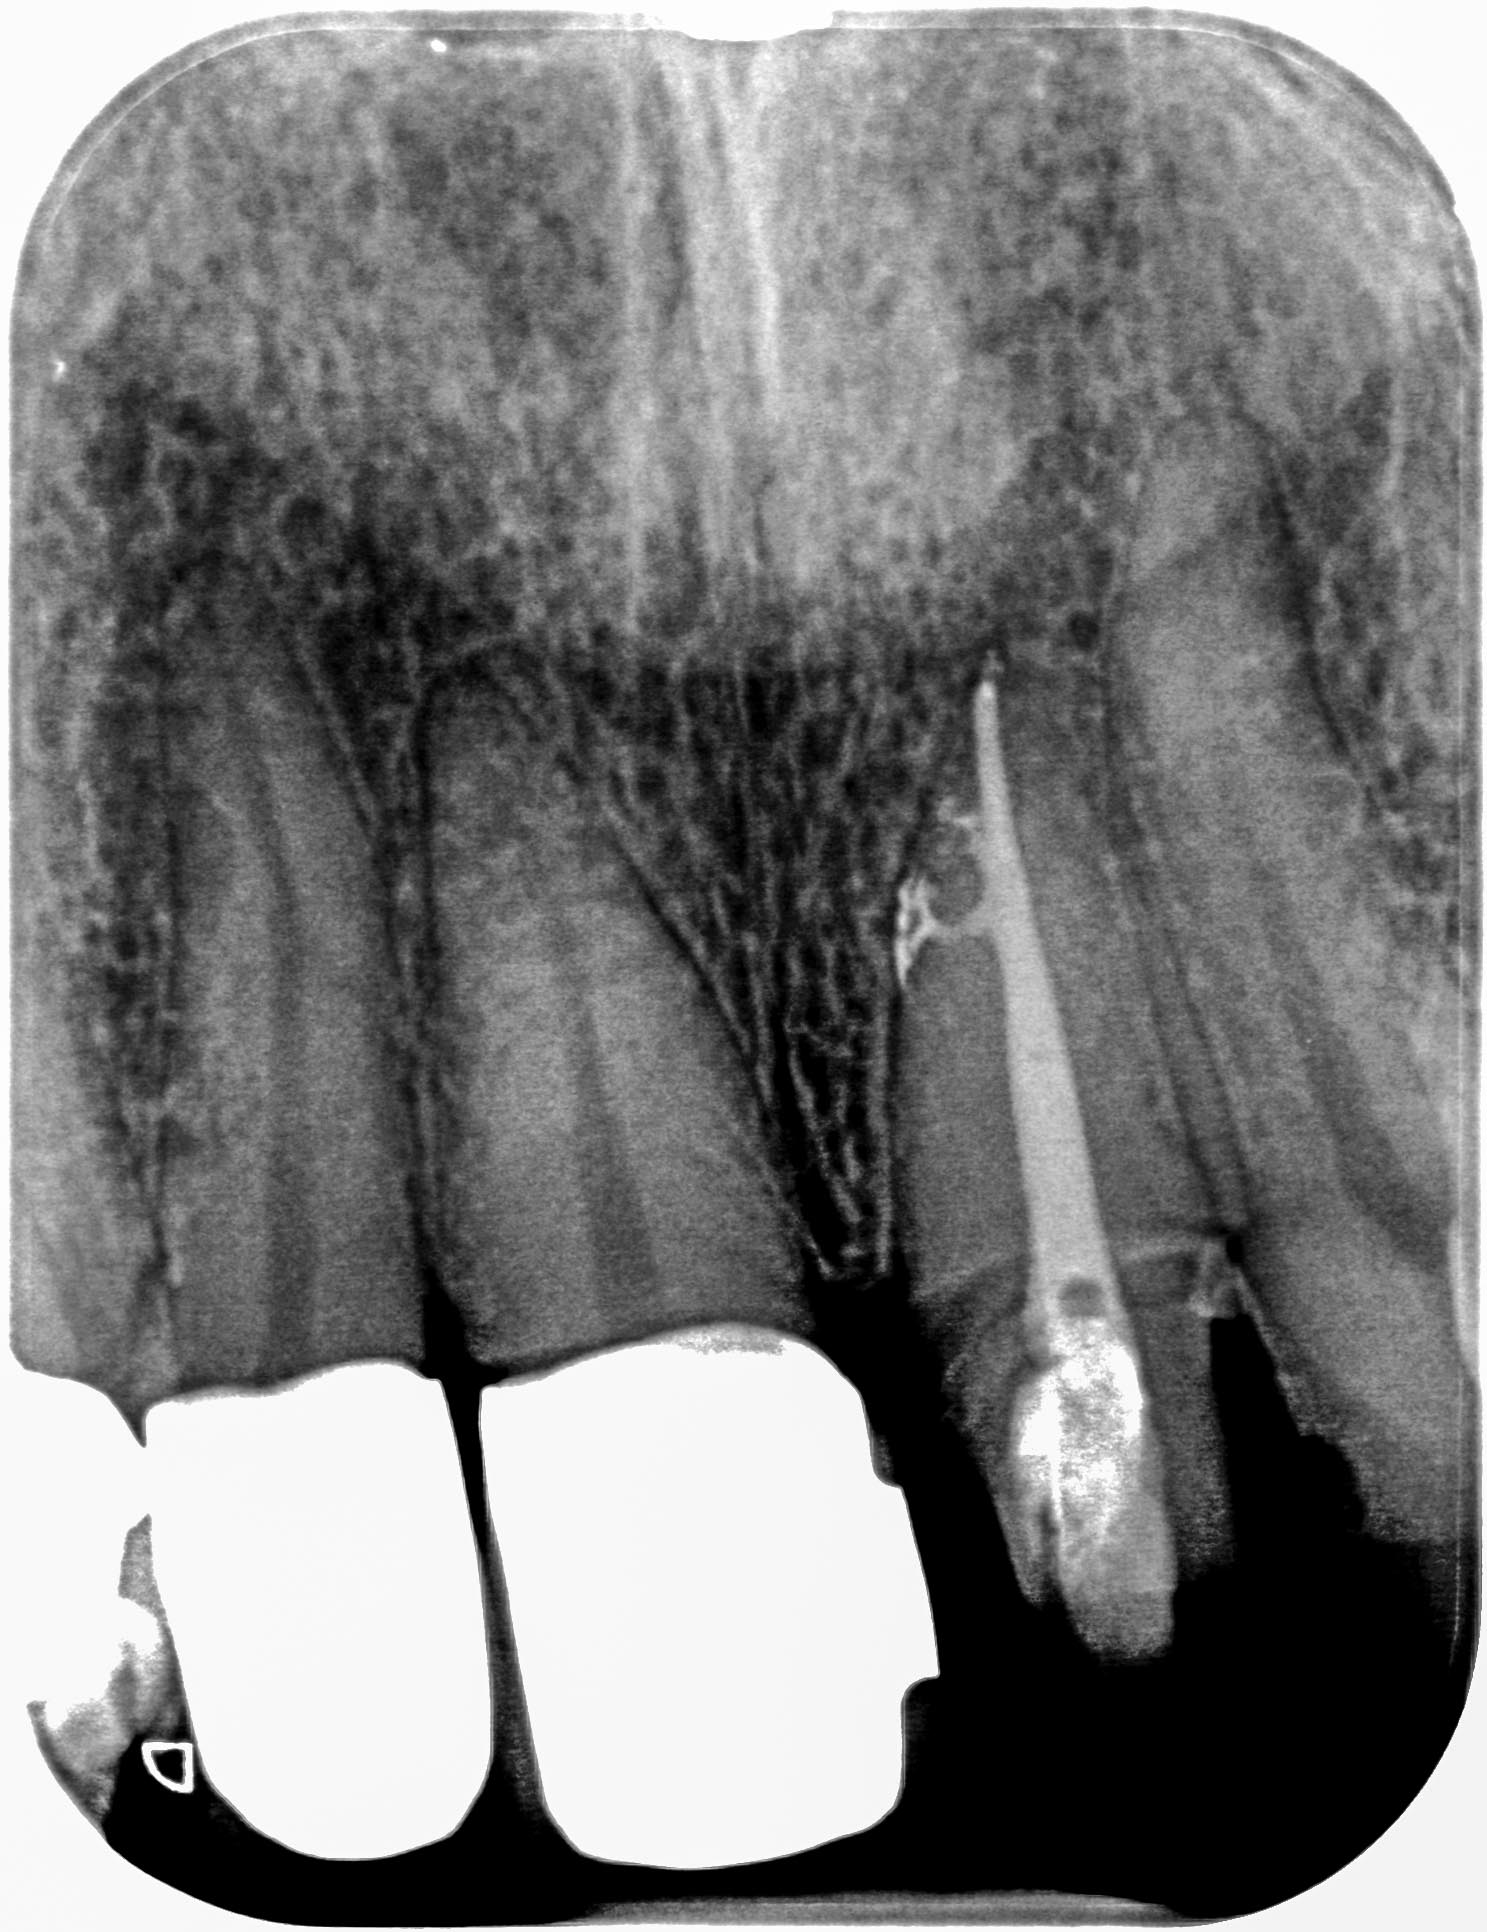

LW_21-1 Veröffentlicht 8. Dezember 2014 am 1487 × 1932 in Was sichert den Behandlungserfolg ? 21, Zustand nach WF- Revision